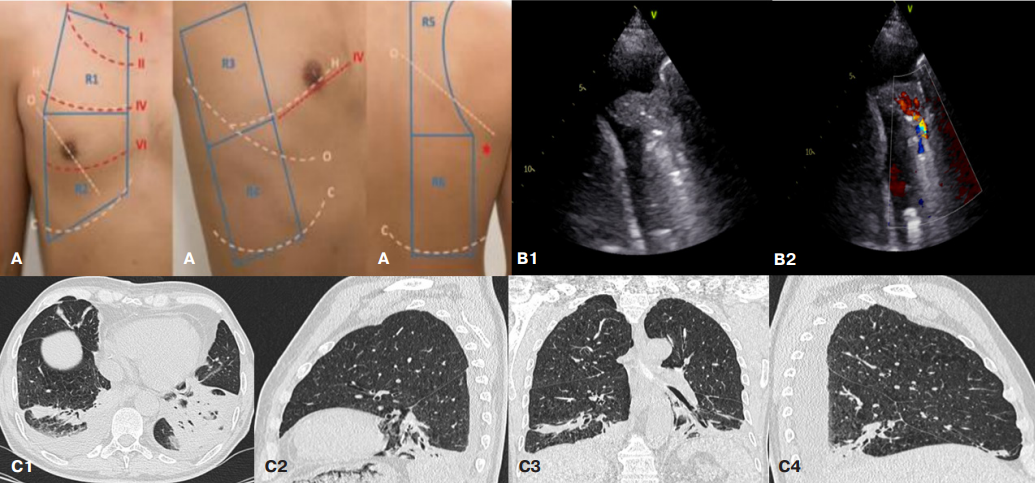

На 7 сут. после операции у пациента появилась лихорадка >38 C и малопродуктивный кашель, при аускультации сухие рассеянные хрипы над нижними отделами легких с обеих сторон, сатурация крови 94% (на атмосферном воздухе). В крови уровень лейкоцитов в пределах нормальных значений (5,58×109/л), умеренное повышение С-реактивного белка (СРБ) до 25 мг/л, скорость оседания эритроцитов (СОЭ) 33 мм/ч. Заподозрена НП, проведено фокусное УЗИ лёгких по 6-точечному протоколу (рис. 1 А). В 7 межреберье по лопаточной линии с обеих сторон в проекции нижней доли лёгких выявлено утолщение плевры до 3,5 мм, участки субплевральной консолидации с фенокопией воздушной бронхограммы размерами справа 57×34 мм, слева 40×17 мм неоднородной эхогенности с выраженной артерио-венозной васкуляризацией (скорость артериального кровотока 30-60 см/с). Подвижность нижнего края легких снижена. Около зон консолидации с обеих сторон — множественные (от 3 до 7 в поле зрения), в т.ч. сливные, В-линии. В зонах, удаленных от участков консолидации, над задними, передними и боковыми отделами легких — единичные В-линии. В плевральных полостях жидкость с обеих сторон (справа 260 мл, слева 330 мл) (рис. 1 В). Заключение: участки консолидации с артериальной васкуляризацией в проекции нижних долей лёгких с обеих сторон с мультифокальными сливными В-линиями около них (признак, патогномоничный для двусторонней пневмонии), в сочетании с двусторонним легочным интерстициальным синдромом и гидротораксом. Выполнена КТ ОГК (рис. 1 С). Выявлено наличие жидкости в плевральных полостях (350 мл справа и 70 мл слева), в нижних отделах с обеих сторон участки коллабирования базальных отделов легких, в проекции 9 и 10 сегментов перибронхиальная инфильтрация с воздушными просветами бронхов, что соответствует двусторонней нижнедолевой пневмонии. В соответствии с национальными рекомендациями [6] была назначена антибактериальная терапия НП с положительной динамикой, на 14 сут. после оперативного вмешательства пациент выписан.

Рис. 1. Лучевые методы исследования легких пациента Р.

Примечание: А — области ультразвукового сканирования лёгких с использованием 6-точечного протокола, В — УЗИ (В1 — правая задняя нижняя зона, В-режим, В2 — правая задняя нижняя зона, режим ЦДК), С — спиральная КТ ОГК (С1 — аксиальная проекция в легочном окне на уровне базальных сегментов, С2 — сагиттальная проекция в легочном окне левого легкого, С3 — коронарная проекция в легочном окне, С4 — сагиттальная проекция в легочном окне правого лёгкого).